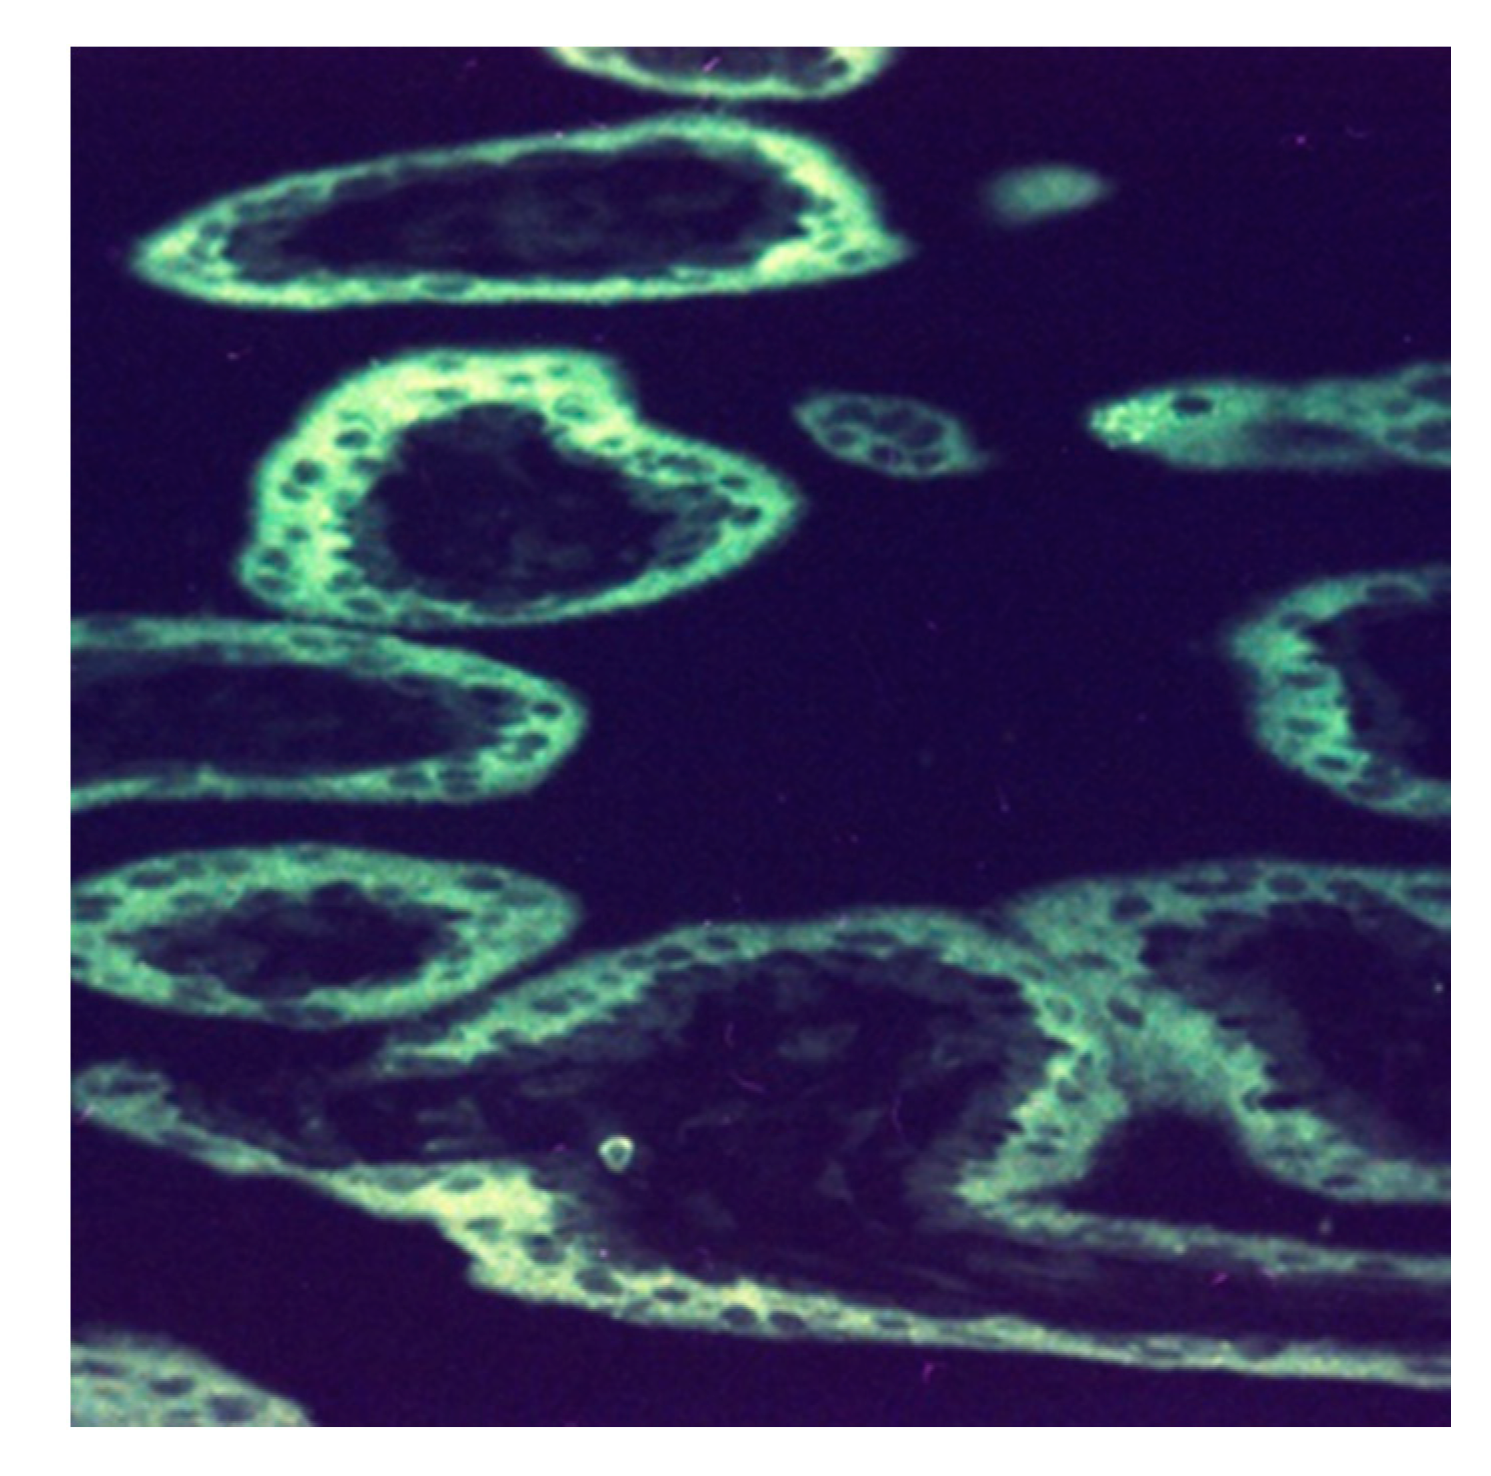

Figure 5.

Human placental lactogen secretion from the syncytiotrophoblast at 12 w 2 d (×320). The fluorescent reaction with fluorescein-isothiocyanate (FITC)-labeled anti-hPL (rabbit) is confined to the syncytiotrophoblast layer of chorionic villi, thus creating the image of a “white ring”.